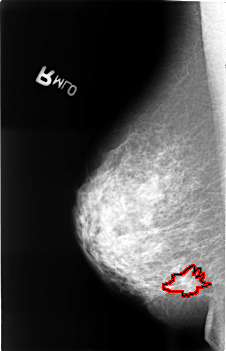

FILE: B_3399_1.RIGHT_MLO.OVERLAY

TOTAL_ABNORMALITIES 1

ABNORMALITY 1

LESION_TYPE CALCIFICATION TYPE PUNCTATE DISTRIBUTION CLUSTERED

LESION_TYPE MASS SHAPE IRREGULAR-ARCHITECTURAL_DISTORTION MARGINS SPICULATED

ASSESSMENT 5

SUBTLETY 3

PATHOLOGY MALIGNANT

TOTAL_OUTLINES 1

BOUNDARY

RIGHT_MLO LINES 4552 PIXELS_PER_LINE 2928 BITS_PER_PIXEL 12 RESOLUTION 50 OVERLAY